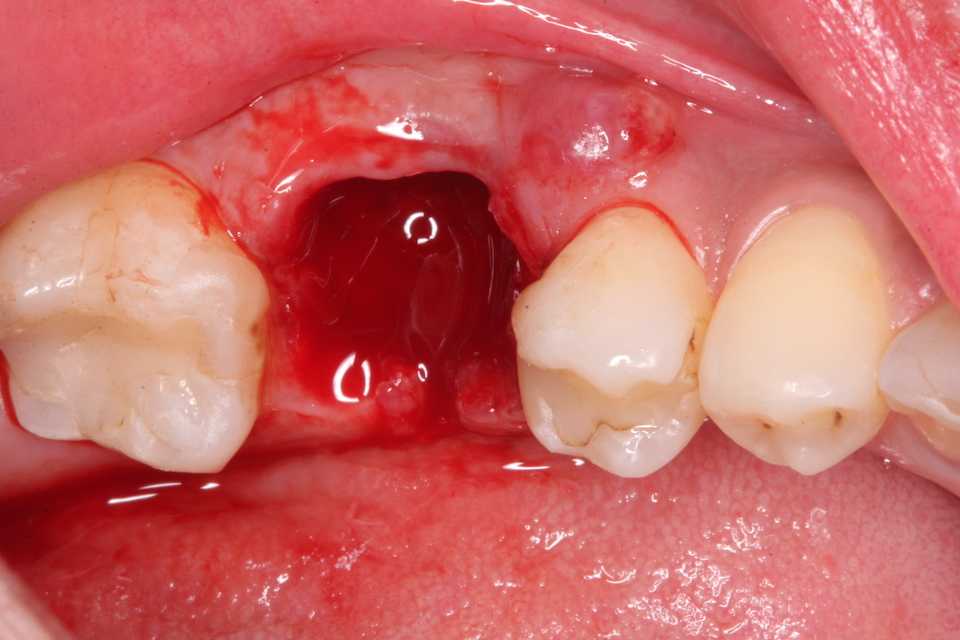

70代女性、右上2、歯根破折、左上2、SK脱離このところの異常な熱波続きでついふらふらと意識が遠のき、顔面から転倒。歯が折れてしまった。特に右上は歯根も破折しているので、通常は抜歯するしかないのだけれど、α-TCPで接着固定して、それをCRで巻いてついでに歯冠も作った。破折歯根上のCRということです。転倒前beforeafter3〜3をスーパーボンド併用で連結固定している。